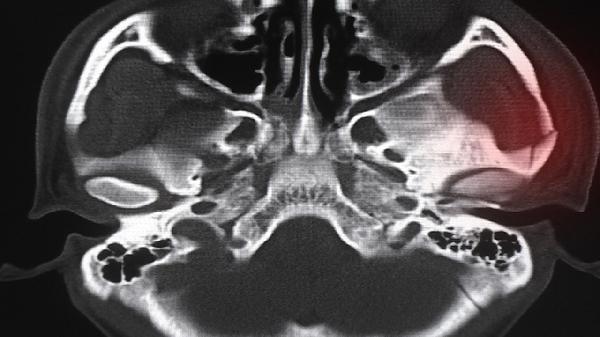

5、疗效评估

常规用药3个月后应通过X线或CT评估骨赘变化情况,若出现关节活动度持续恶化需考虑调整治疗方案。疼痛症状缓解后不可擅自增量,过度用药可能导致骨代谢紊乱。突发关节肿胀或持续性麻木需警惕药物相关性关节滑膜炎。